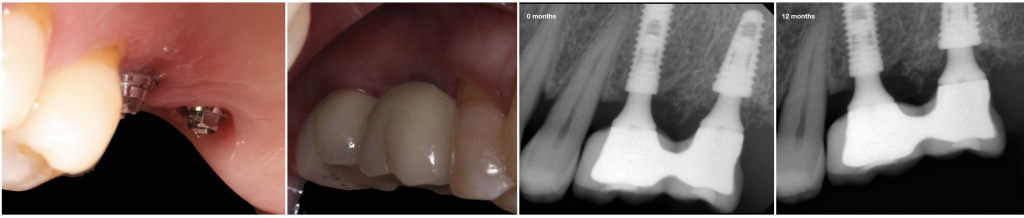

Fig. 4- Follow up after 12 months. Peri-implant soft and hard tissue was well preserved.

During the observation period (12 months), the four implants were osseointegrated, and functional, mechanical or biological complications were not reported. The volume of the soft tissues and the horizontal ridge were lower than in the initial situation. However, the radiographic controls showed bone over the implant platform.

Immediate implant placement into a fresh molar extraction socket is possible with excellent results with the appropriate implant, with or without grafting materials. The introduction of the definitive abutment at the same time is possible with primary stability, and it simplifies the restorative procedure, minimize the biological changes during the healing period.